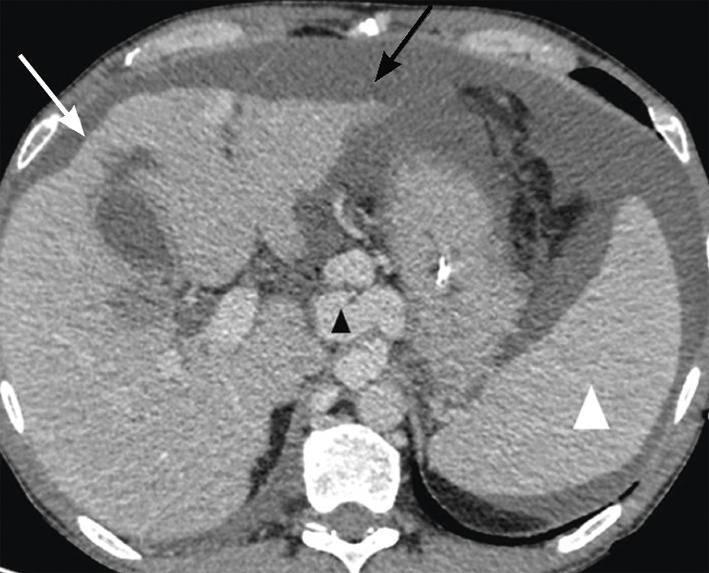

Un patient de 60 ans, éthylique chronique, vient pour amaigrissement et fatigue avec vomissements et distension abdominale. Le scanner au temps portal révèle une dysmorphie hépatique (contours bosselés) liée à une hépatopathie chronique (fig. 4 ; flèche blanche). S’y associent une ascite abondante (flèche noire), des voies de dérivation veineuse (tête de flèche noire) et une splénomégalie (tête de flèche blanche), traduisant une hypertension portale décompensée.

Un patient de 60 ans, éthylique chronique, vient pour amaigrissement et fatigue avec vomissements et distension abdominale. Le scanner au temps portal révèle une dysmorphie hépatique (contours bosselés) liée à une hépatopathie chronique (